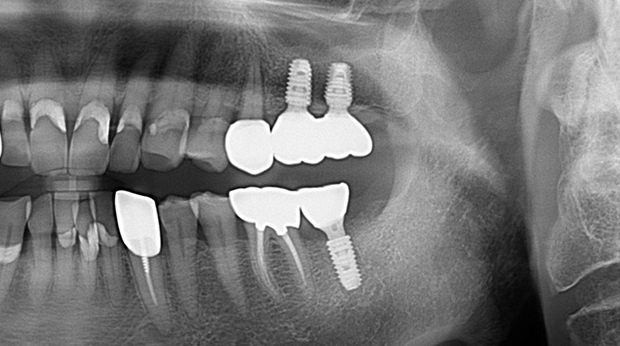

의식하진정법(수면마취)/임플란트

임플란트와 사랑니 발치는 외과적 시술로 잇몸을 절개하는 외과적 시술은

짧으면 짧을 수록 시술 후 붓기와 통증이 최소화됩니다.

치과의사 경력 14년차 구강외과 전문의가 빠르고 안전하게, 아프지 않게 수술해 드립니다.

치과경력 14년차 구강외과 전문의

연세대학교 치과대학 구강외과 임상 조교수